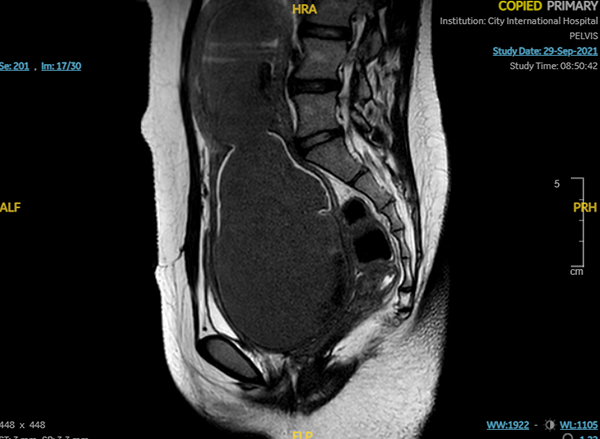

Hình chụp nhìn từ bên cạnh. A: Phần âm đạo ứ máu. B phần tử cung ứ máu